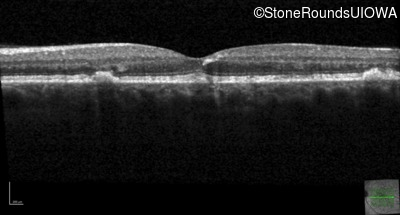

Age at visit: 49 years

Age at visit: 49 years (Visit 2)